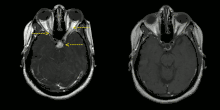

Image de droite : IRM cérébrale avec contraste montrant une résolution proche de celle du rehaussement après traitement.

L’IRM avec rehaussement au gadolinium est l’examen de neuroimagerie le plus utile. Il peut montrer une amélioration de la pie-mère ou des lésions de la substance blanche qui peuvent ressembler aux lésions observées dans la sclérose en plaques[1].